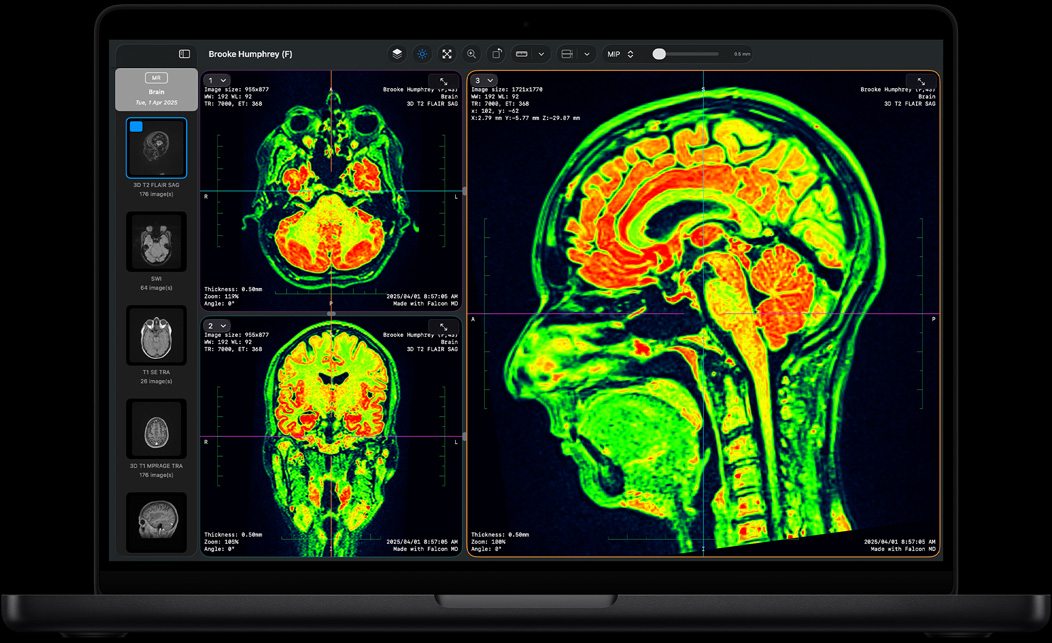

S’il vous faut plus de puissance, la M4 Pro accélère tout ce que vous faites, de la modélisation à la conception de bases de données en passant par le séquençage ADN. Que vous optiez pour le modèle 14 ou 16 pouces, le MacBook Pro avec M4 Pro gère sans difficulté les workflows les plus exigeants et offre des performances graphiques plus rapides pour le rendu et l’animation 3D.

Falcon MD

Performances plus rapides pour le rendu dans Redshift17

Performances plus rapides pour la resynchronisation vidéo dans Topaz Video AI18

Performances plus rapides pour l’appel de base dans MinKNOW d’Oxford Nanopore19

Performances de gaming plus rapides dans World of Warcraft: The War Within20

Simulation de systèmes dynamiques plus rapide dans MATLAB21

Performances plus rapides pour la compilation de projets dans Xcode22

Performances plus rapides pour le Neural Filter et les fonctions dans Adobe Photoshop23

MATLAB

Votre nouveau partenaire de labo. Exécutez des simulations complexes, effectuez des séquençages ADN ou analysez de grands ensembles de données dans toutes sortes d’environnements scientifiques.

MATLAB, Autodesk AutoCAD, NASA TetrUSS, Oxford Nanopore MinKNOW, OsiriX MD, Shapr3D, SurgicalAR, Vectorworks, Archicad et plus.